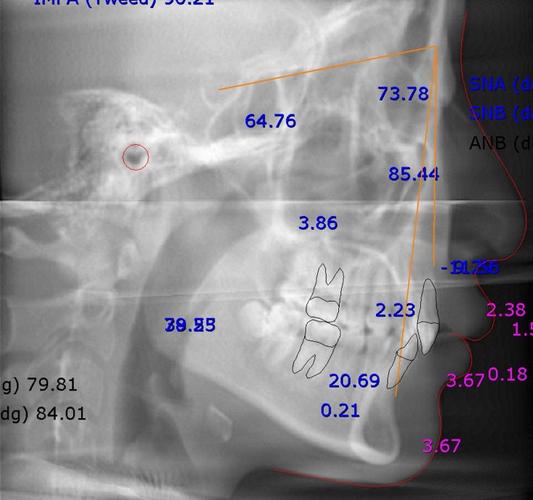

头颅侧位片的解读需通过标志点与测量线实现,以下为核心指标及临床意义(常用正常值范围参考中国汉族人群数据):

(一)骨骼测量指标

| SNA角 | 蝶鞍中心(S)-鼻根点(N)-上牙槽座点(A)的夹角 | 82°±4° | 反映上颌骨相对于颅骨的前后位置:>86°提示上颌前突,<78°提示上颌后缩。 |

| SNB角 | 蝶鞍中心(S)-鼻根点(N)-下牙槽座点(B)的夹角 | 80°±4° | 反映下颌骨相对于颅骨的前后位置:>84°提示下颌前突,<76°提示下颌后缩。 |

| ANB角 | SNA角与SNB角的差值(SNA-SNB) | 2°±2° | 上下颌骨的矢状关系:>4°提示上颌前突或下颌后缩,<0°提示下颌前突或上颌后缩。 |

| MP-FH角 | 下颌平面(MP,通过颏下点与下颌角点的连线)-颅底平面(FH)的夹角 | 32°±3° | 面部垂直高度:>37°提示长面型(下颌平面陡峭),<27°提示短面型(下颌平面平缓)。 |

(二)牙齿测量指标

| U1-NA距 | 上中切牙切端至NA连线的垂直距离 | 4mm±2mm | 上切牙突度:>6mm提示上切牙前突(深覆盖常见),<2mm提示上切牙舌倾。 |

| U1-NA角 | 上中切牙长轴与NA连线的夹角 | 22°±5° | 上切牙倾斜度:>28°提示上切牙唇倾,<16°提示上切牙舌倾。 |

| L1-NB距 | 下中切牙切端至NB连线的垂直距离 | 2mm±2mm | 下切牙突度:>4mm提示下切牙前突(反颌或深覆盖常见),<0mm提示下切牙舌倾。 |

| L1-NB角 | 下中切牙长轴与NB连线的夹角 | 30°±6° | 下切牙倾斜度:>37°提示下切牙唇倾,<23°提示下切牙舌倾。 |

| IMPA角 | 下中切牙长轴与下颌平面(MP)的夹角 | 95°±6° | 下切牙倾斜度:>102°提示下切牙唇倾(易导致下前牙拥挤),<88°提示下切牙舌倾。 |